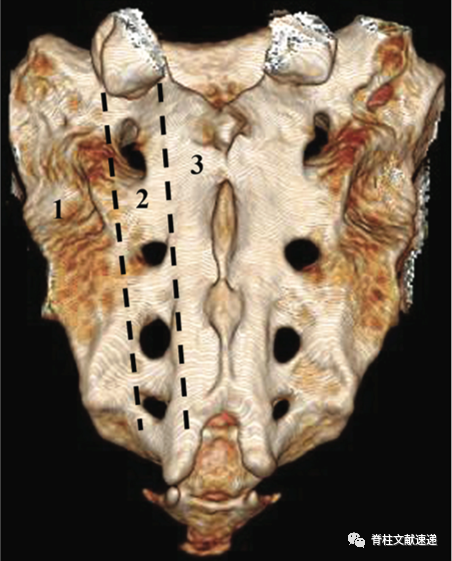

早期研究报道的骶骨衰竭骨折的发生率为1-1.8%,近期的一项研究调查了250 名到急诊科就诊并CT成像的疑似骨盆损伤患者。在被诊断患有骨盆骨折的 46 名患者中,11 名患者 (4.4%) 被发现患有骶骨衰竭骨折。多见于平均年龄 70-75 岁的患者。下图中1区为骶骨衰竭骨折常见区域。

局部疼痛常见,压痛叩击痛常阳性,部分患者存在体位变化时疼痛,与骨质疏松性胸腰椎骨折相似。骶骨衰竭骨折常见于骶骨翼。X线和CT不易诊断,MRI和骨扫描是推荐的影像学检查,敏感度接近100%。成像特点和骨质疏松性胸腰椎压缩骨折类似,MRI T1低信号,T2和脂肪抑制像呈片状高信号。如下图所示,骶骨MRI显示双侧骶骨翼冠状图像上信号增加,表明双侧骶骨翼骨折引起明显的骶骨水肿。